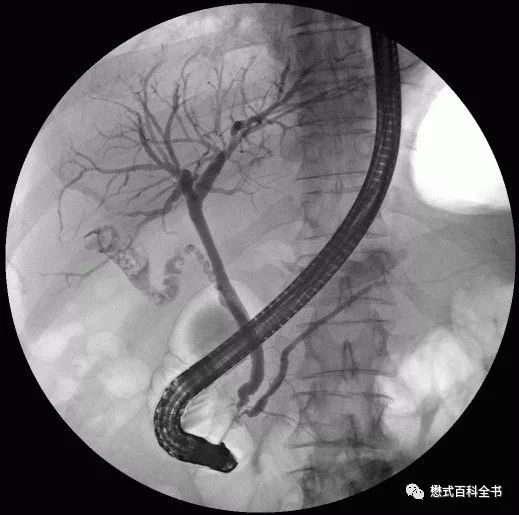

图1:ERCP示意图

和MRCP类似的一个单词叫做ERCP(Endoscopic Retrograde CholangioPancreatography),翻译过来就是(经内镜)逆行性胰胆管造影术。Endo-是内、在内的前缀,-scopic表示观测、视察,当然endoscopic这个词本来就是内窥镜的,用内镜的方式的意思。Retro-是一个使用比较多的前缀,代表向后的,回顾的,*退倒**的。大家还记得我们的回顾性心电门控是怎么表述的吗?Retrospective,回顾性研究,回顾性分析都是这个前缀。grade这个单词大家熟悉,可以理解为年级、级别、阶段。

retrograde就很好理解了,为了信达雅和结合技术把它翻译为逆行性的。而同样的单词cholangiopancreatography在MRCP中翻译为成像,在ERCP中翻译为造影术更恰当。因为ERCP是一种有创性的手术方式,并且会注入造影剂以使胆囊及胆管系统显影,所以用造影术是比较合适的。